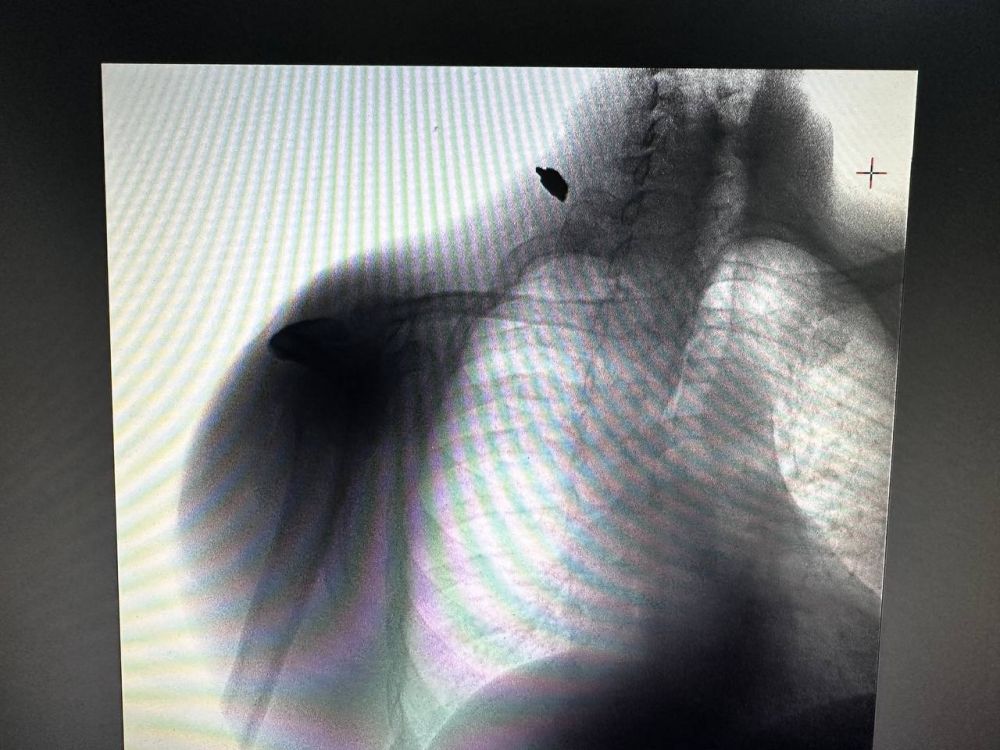

Врачи Федерального медико-биологического агентства России спасли жизнь пациенту с осколочным ранениемБригада скорой медицинской помощи Херсонской области доставила в Нижнесерогозскую центральную районную больницу мужчину с осколочным ранением...